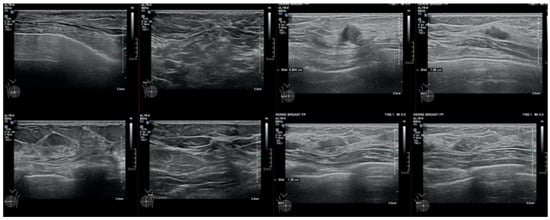

We report the case of a 47-year-old pre-menopausal Caucasian woman who presented to the Policlinico Umberto I hospital in Rome, with a 6-month history of subjective dizziness, oscillopsia, instability, imbalance, blurred vision, and photophobia, accompanied by severe vomiting, which resulted in severe weight loss (16 kg over 7 months) (Table 1). The medical history was significant for only hypothyroidism and her family history was positive for a sister with breast cancer. Clinical examination of our patient revealed marked fluctuations without prevalence to the side during Romberg and Fukuda tests, both with open and closed eyes. In video-oculoscopy (Supplementary Materials Video S1), the assessment of extraocular motility demonstrated isolated and intermittent episodes of low-amplitude, high-frequency horizontal saccades occurring without an intersaccadic interval, consistent with the clinical presentation of ocular flutter []. A comprehensive evaluation was performed, including contrast-enhanced brain Magnetic Resonance Imaging (MRI) (Figure 1), brain Computed Tomography (CT) scan (Figure 2), ophthalmological assessment, viral serology, autoimmune panel, complete blood count, and assessments of thyroid, renal, coagulation, hepatic function, vitamin D and B12 levels; all results were within normal limits. Paraneoplastic syndrome (ENS) sometimes precedes the diagnosis of cancer, necessitating a screening to detect an unidentified tumor. After excluding all other potential causes of the neurological symptomatology, a paraneoplastic origin was considered. Paraneoplastic autoantibody panels (anti-Ri, anti-Yo, anti-Hu, anti-CV2.1, anti-Amphiphysin, and anti-Ma2/Ta) resulted positive for anti-Ri onconeural antibodies with a value of 1:126 (51–256 strong positivity). A whole-body CT scan revealed multiple solid non-calcific nodules (at least 4 in the right breast QQEE), the largest measuring 13 × 9 mm, and right axillary lymphadenopathy measuring 24 mm (Figure 3). Mammography showed at least three nodular opacities with an irregular shape in the external superior quadrant of the right breast. The biggest ones were 13 mm (with intranodular microcalcifications) and 12 mm (BIRADS 5) (Figure 4). The breast ultrasound confirmed three solid irregular hypoechoic nodules measuring 11 mm, 9 mm, and 12 mm, as well as some right axillary lymphadenopathy, the largest measured 25 mm (Figure 5). Histological examination of an ultrasound-guided biopsy revealed invasive carcinoma “no special type” (NST) according to the 2019 World Health Organization (WHO) classification, with a grade 2 histology (G2) with occasional outbreaks of ductal carcinoma and axillary lymph node metastasis. Additionally, a bone scan revealed no evidence of the disease’s metastatic localization (Figure 6). A multidisciplinary team decided to proceed with a right mastectomy and a right axillary dissection. The final histopathological report showed an invasive multifocal NST grade 2 carcinoma, positive for ER (98%), PR (80%), Ki67 (32%) and negative for HER2 (Luminal B HER2 negative). The resection margins were free of neoplastic infiltration. Two of the 14 lymph nodes were positive for invasive carcinoma. The final staging was G2 pTle pNla (2/14) MO, stage IIA. The patient received hormone therapy (Exemestane 25 mg daily and Decapeptyl 3.75 mg daily) due to high hormone receptor expression. Surgical treatment of the primary tumor did not improve neurological symptoms, prompting the patient to undergo intravenous steroid therapy; however, this also did not lead to any clinical improvement. The patient was evaluated at 2, 6, 12 and 24 months with clinical, radiological and serological examinations. On vestibular examination 2 months post-surgery, subjective dizziness and instability persisted. On video-oculoscopy, the patient presented ocular flutter with intermittent horizontal saccades especially in the lateral gaze. Total body CT scan (Figure 7) and breast ultrasound (Figure 8) at 2 months were negative for neoplastic recurrence or metastases. Serology for anti-Ri antibodies remained positive. Six months after surgery, the patient, who had been on Prednisone 50 mg/day, was admitted to the neurology department of another hospital. Patient reported an improvement in headache and a reduction in the frequency of emesis, but no improvement of the ocular and vestibular symptoms. The neurological examination documented oculovestibular syndrome with ocular flutter that was not inhibited by fixation, forcing the patient to keep her eyes closed, ataxia, head and trunk tremor, hypomimic facies, hypertonia in the right upper limb with difficulty in movements of the right hand, difficulty getting up from the chair without support, instability in open and closed eyed Romberg test, moon facies due to iatrogenic Cushing’s, slow, diprosodic and hypophonic speech. During admission, an MRI of the brain and brainstem was performed, which showed a slight enlargement of the peri-brain spaces in the frontal area and of the peri-brain spaces in the cerebellar area, possibly indicative of initial atrophy. Blood tests confirmed the presence of anti-Ri antibodies. Considering the immune-mediated genesis of the paraneoplastic syndrome, the patient underwent five sessions of plasmapheresis followed by a course of intravenous immunoglobulin (0.4 g/kg/day) with a slight and temporary clinical improvement. Due to the presence of a mild right rigid-kinetic hemi-syndromes with associated hypomimia and hypophonia, a genetic study for Parkinson’s disease was conducted and L-DOPA therapy was prescribed, which was then discontinued as the patient reported worsening symptoms. The patient underwent brain SPECT with receptor tracer to evaluate the presynaptic dopaminergic system the basal ganglia, which showed no impairment of the nigrostriatal presynaptic dopaminergic system. Due to the lack of response to chronic steroid therapy and the development of clinical signs of iatrogenic Cushing’s, following endocrinological consultation, the dosage of Prednisone was progressively reduced and then replaced by Cortone Acetate. Bone mineral density was normal. After one month, the patient was transferred to a rehabilitation center to undergo neuromotor and vestibular rehabilitation until the patient was transferred back to the prior neurology department due to a clinical worsening, in particular of the eye complaints. The patient was unable to perform more than a few steps without support, showed multidirectional fluctuations on the Romberg test with trunk instability. At eye opening there was persistence of the ocular flutter, with mydriatic pupils (left > right) and a cloudy but present response to direct light stimulus. The other cranial nerves were intact. Thermal tactile and pain sensitivity were preserved. Osteotendinous reflexes were brisk and symmetrical in the upper limbs and hypotensive in the lower limbs. Coordination tests (index-nose, index-index, finger-tapping), revealed mild motor impairment on the right side with kinetic and postural tremor and fine tremors in the upper limbs. During hospitalization, the patient underwent a new course of plasmapheresis (four sessions in 8 days) combined with intravenous immunoglobulins (0.4 g/kg/day for 4 days) with slight clinical benefit. Due to the need for chronic immunosuppressive treatment, oral therapy with Azathioprine at an initial dosage of 25 mg/day, later increased to 50 mg, was administered. A contrast-enhanced MRI of the brain and cervical spine was performed, which showed essentially unchanged findings compared to the previous check-up, including a modest enlargement of the peri-brain spaces in the frontal area and peri-foliar spaces in the cerebellum, expressing initial signs of atrophy. Slight clinical improvement was documented during hospitalization, particularly in head tremor and ocular flutter, allowing the patient to fixate, despite the persistence of pathological eye movements. Gait was improved, although the patient remained ataxic. In view of this progress, the patient was again transferred to the neuromotor rehabilitation center for one month at the 12 months follow-up visit, the patient reported a worsening of the oculovestibular syndrome with inexhaustible flutter preventing fixation, worsening of rigidity in the right upper limb and occasional dysphagia. The neurological examination showed dystonic flexion in the right upper limb and plastic hypertonia in the upper limbs bilaterally (right > left), but no hypertonia in the lower limbs. Independent ambulation was not possible. The patient had an intravenous infusion of cyclophosphamide, which brought only slight and transient improvements in symptoms. After 24 months from the surgery, the patient was re-evaluated in our hospital, and a vestibular examination via oculoscopy confirmed the presence of the flutter with horizontal saccades, which were slightly reduced compared to the first assessment in 2022. Vestibulospinal tests revealed a severe postural deficit, with ataxic walking and right upper limb rigidity.

Figure 5. Ultrasonographic image showing irregular, solid, hypoechoic nodules (red lines), suspicious for malignancy. Axillary lymph nodes are also visible (indicated by orange arrows and lines), some of which display altered morphological features.

Figure 8. Absence of radiological evidence of neoplastic recurrence in the 2 months follow-up breast ultra-sound.